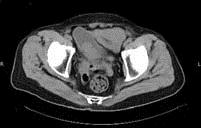

问题 男,74岁,无痛性肉眼血尿1个月余,CT扫描如图所示,该疾病最可能的诊断为 ( )

选项 A、膀胱息肉 B、输尿管囊肿 C、膀胱结石 D、膀胱血块 E、膀胱癌

答案 E